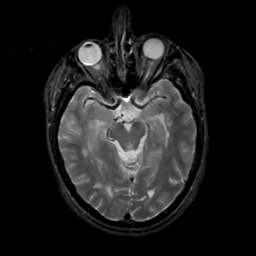

MR Study #4, March 3, 1991 -- Slice #20

[Home][Help][Clinical][Tour 1][Tour 2] Slice 20